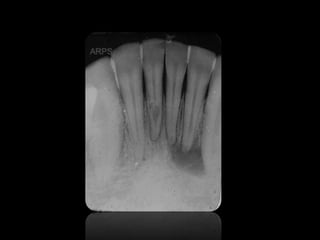

REABSORCIONES ÓSEAS

REABSORCIÓN DENTAL EXTERNA

REABSORCIÓN DENTAL INTERNA